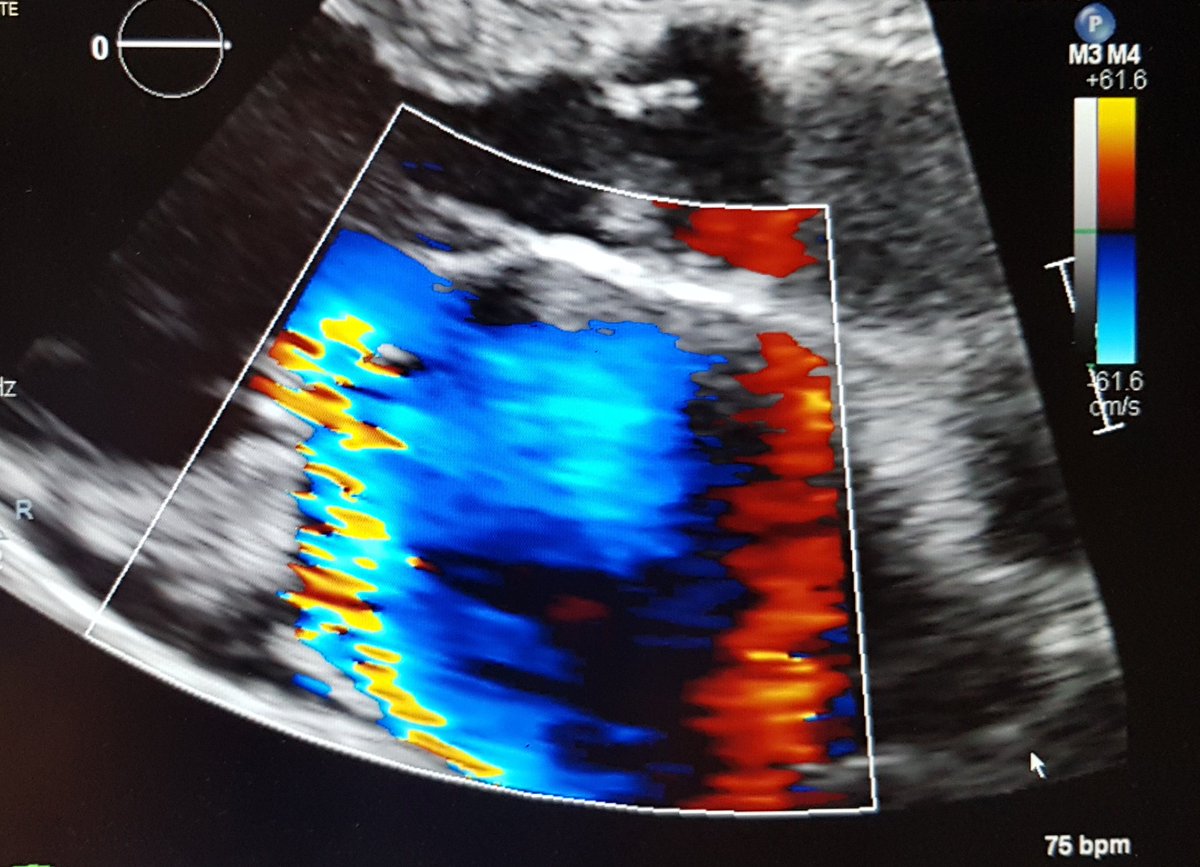

2. Systolic Anterior Motion (SAM)

SAM of the AMVL tends to (not always) produce posteriorly directed MR; important to remember that SAM is not the only reason a HCM patient may have MR

Here you can see the posteriorly directed MR jet on colour Doppler imaging